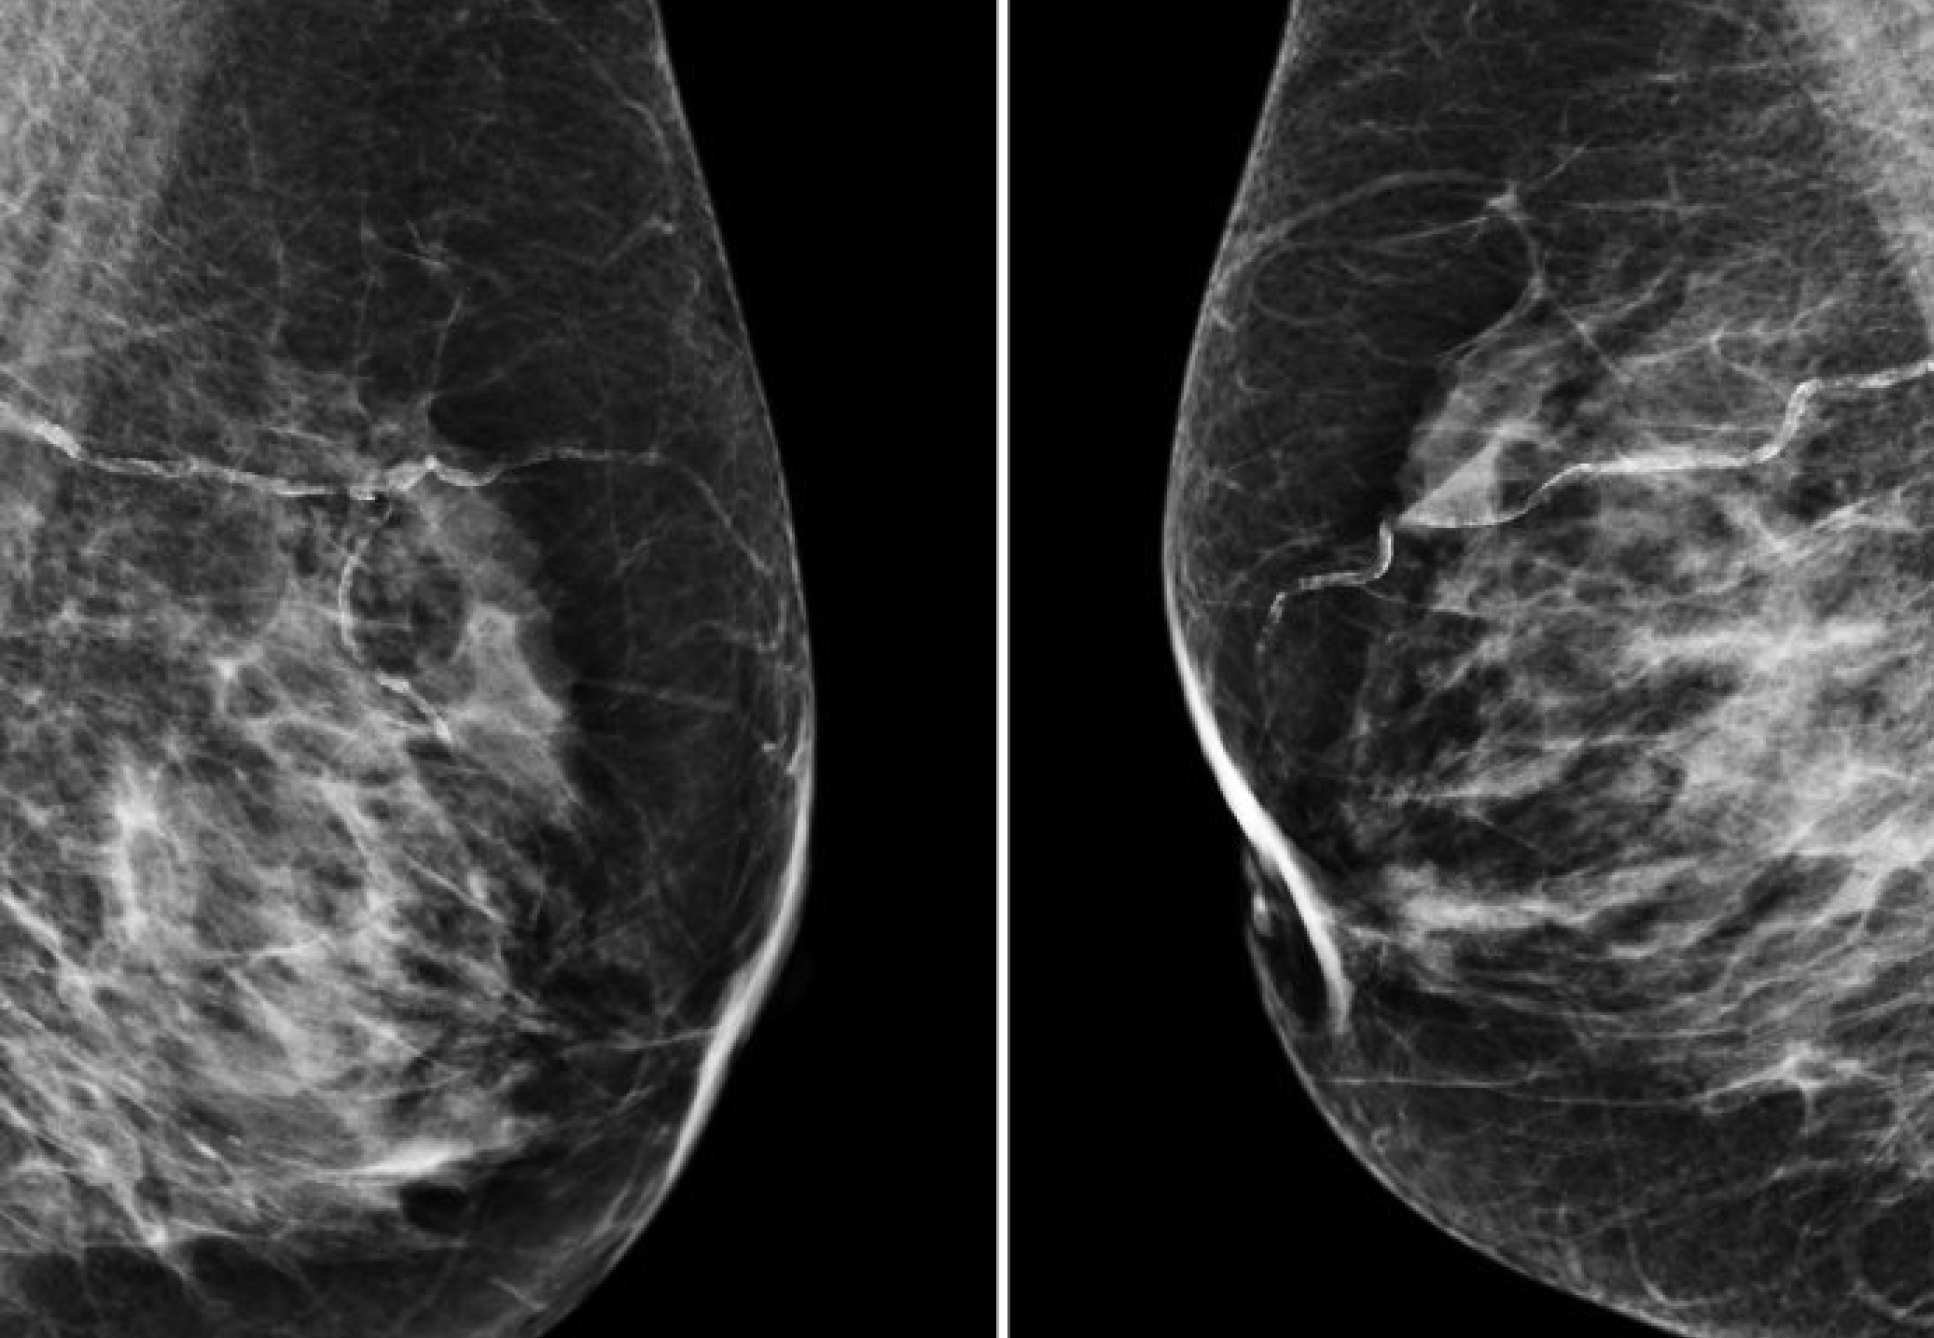

"It is also totally interdisciplinary and understands that health outcomes are very much the result of what happens in different disciplines. We see that in the linking together of AI and clinical medicine in some of the work that’s being done to improve the quality of screening processes.